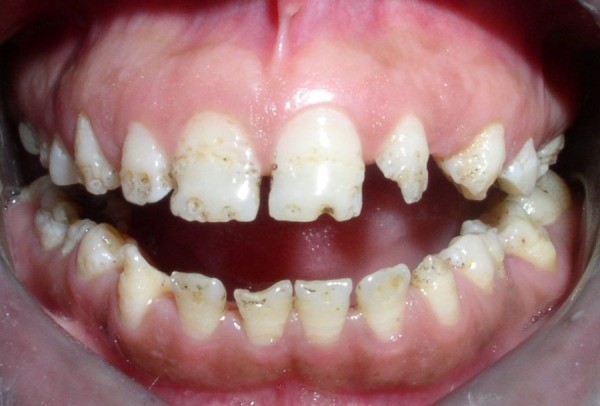

بسته به شدت، این نقص میتواند مانند یک تورفتگی کوچک در دندان به نظر برسد یا چند دندان را در سراسر دهان تحت تاثیر قرار دهد. ممکن است تغییر رنگ دندان موضعی باشد، یا تمام دندان میتواند به رنگ قهوهای تیره درآید. این امر میتواند دهان و دندان را فوقالعاده حساس کند، به خصوص برای کودکانی نوپا که تازه یاد گرفتهاند که چگونه احساسات خود را بیان کنند.

هیپوپلازی مینای دندان میتواند به دو روش بر روی دندانها تأثیر بگذارد. این نقص گاهی به عنوان یک ساختار از دست رفته فیزیکی دندان شناخته میشود و میتواند به صورت حفره ها، شیارها یا فقط قسمتهایی از دست رفته در تاج دندان باشد. اما در روش دوم، این موضوع سبب کمبود محض ماده معدنی مینای دندان است. اگر این امر به اندازه کافی شدید باشد به دندان فرد، ظاهری شفاف خواهد داد، و اگر خفیف باشد رنگ دندان حفظ میشود.

علائم قابل مشاهده این عارضه شامل لکههای سفید، حفرهها و شیارهای سطح خارجی دندانها است.

- حفرهها، شیارهای کوچک روی دندان

- لکههای سفید

- لکههای زرد مایل به قهوهای (جایی که لایه زیرین عاج دیده میشود)